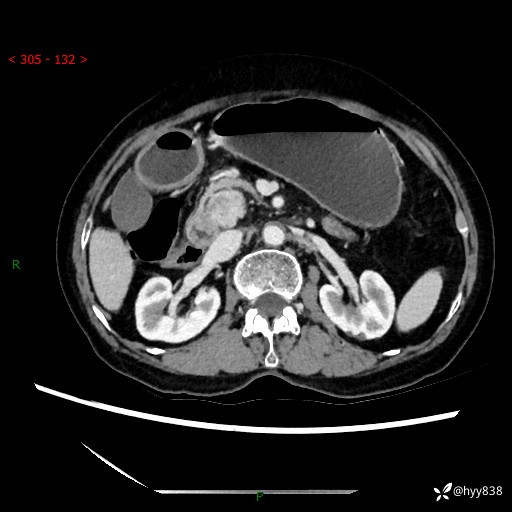

71岁/女,腹痛1月余。腹膜后肿物,间质瘤 VS 副节瘤 VS 平滑肌肉瘤---(有结果)

【患者信息】:71岁/女

【主诉】:腹痛1月余

【现病史及既往史】:患者于1月前无明显诱因出现右下腹部疼痛不适,呈阵发性隐痛,尚可耐受,放射至后背部及腰部疼痛,伴排便困难,不伴其它部位疼痛,无嗳气,无不洁饮食,无黑便,无恶心、呕吐、腹胀腹泻、呕血、发热、寒颤、厌油、黄疸,多次就诊于当地区太湖医院拍片示: 行抗炎等对症支持治疗,效果尚可。现患者上述不适症状明显进一步加重,为求进一步治疗遂来我院门诊就诊,门诊以“十二指肠肿瘤?”收住我科。 起病以来,精神、睡眠可,食欲可,大便异常、小便正常,体力、体重无明显下降。

【检查】:腹部CT增强扫描(外院CT平扫)